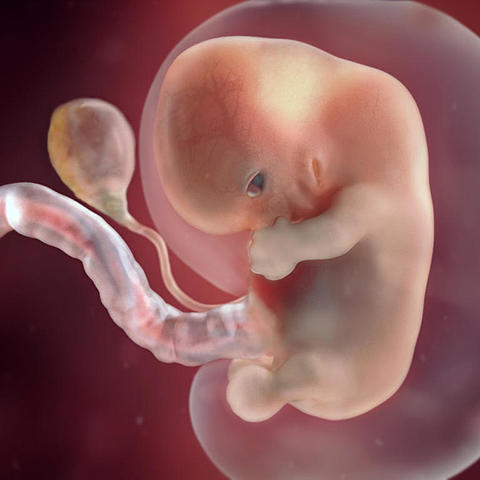

• Semana 8

Semana 8

-Los brazos y las piernas se han alargado y se pueden distinguir las áreas de los pies y de las manos.

-Las manos y los pies tienen dedos (dígitos), pero pueden aún estar adheridos por membranas.

-El cerebro continúa su desarrollo.

-Los pulmones comienzan a formarse.

-Aun se encuentra la cola pero es gruesa y corta.

-Aparece el plexo vascular cuero cabelludo.

-Osificación miembros inferiores (fémur).

*Desaparece la cola.